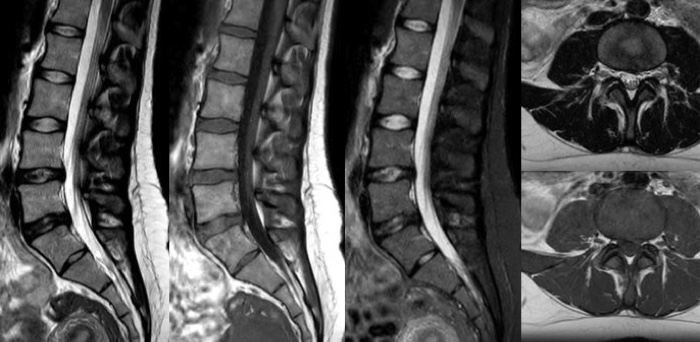

Turn images into answers – 50% faster

Put time on your side with Compressed SENSE to reduce scan time up to 50%2 with virtually equal image quality. Create exceptional MR images with 60% higher resolution for confident diagnosis.

Quality images for quality diagnoses

Our lightest Breeze coils bring extraordinary versatility to imaging challenging anatomies and the smallest joints. A large 55cm field-of-view and premium SNR add to the exceptional image quality.